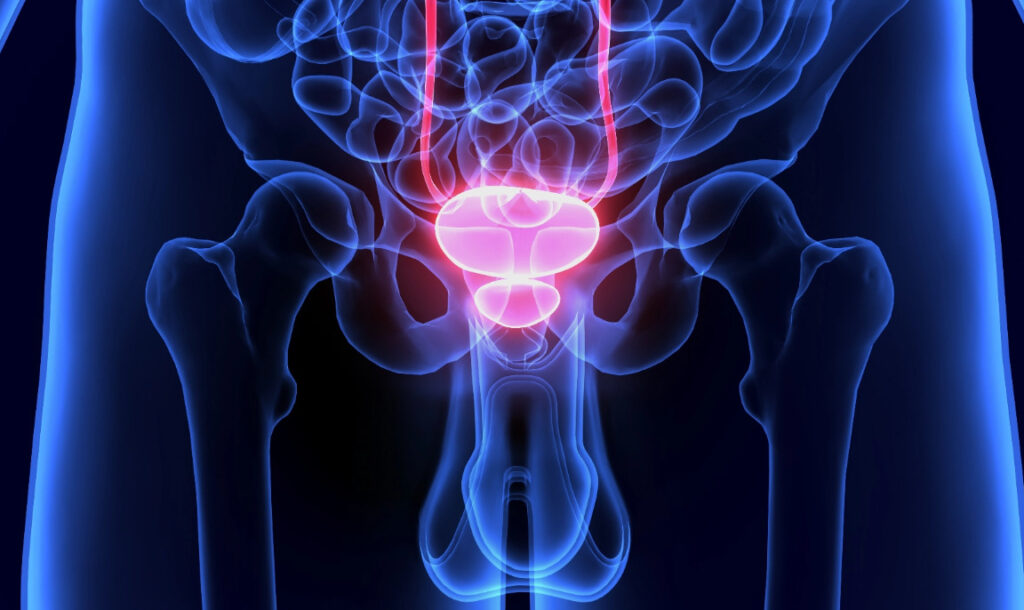

۵. سرطان پروستات

سرطان پروستات یکی از شایعترین سرطانها در مردان بالای ۵۰ سال است.

علائم اولیه:

- تکرر ادرار بهویژه در شب.

- جریان ادرار ضعیف یا متوقف شونده.

- خون در ادرار یا منی.

- درد در ناحیه پایین کمر، لگن یا رانها.

- احساس پر بودن مثانه حتی بعد از ادرار.

نکات کاربردی:

- آزمایش PSA و معاینه رکتال دیجیتال (DRE) برای تشخیص زودهنگام مهم هستند.

- مردان بالای ۵۰ سال یا با سابقه خانوادگی باید غربالگری منظم داشته باشند.